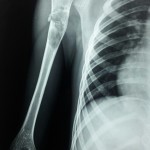

A 72 year old lady sustained a hip fracture. Which of the following is the ideal implant for her?

This is a Classic Reverse Oblique Fracture. And a cephalomedullary system like the Proximal Femoral Nail is the Rx of choice.